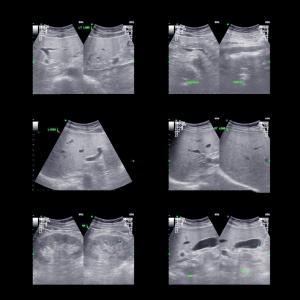

Coup d’accélérateur pour la formation à l’ultrasonographie ciblée

Réalisée au lit du malade, cette méthode diagnostique non invasive et non irradiante est utilisée comme un complément à l’évaluation des patients et des patientes.